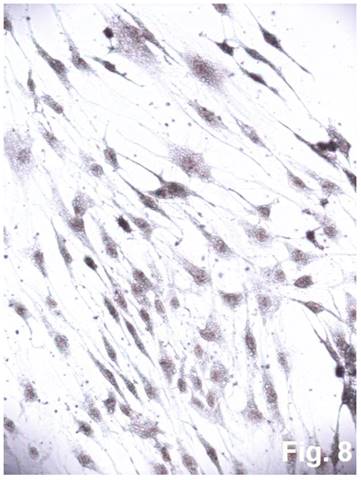

Figure 8

Cultured cells from idiopathic scoliosis concave side (the top of the deformation) stained according to Cajal. x200.

The cells isolated from the concave side growth plates of the deformity (scoliosis apex) were represented by several types (Figures 4a and 4b). The first type cells were large multipolar cells with one long axon and numerous branching short processes (Figure 5a). At the center of these cells, the spherical nucleus with 1-2 nucleoli was located. Granular network (Nissl substance) was detected in the cytoplasm of the cells including processes. We found the same cells with a large oval nucleus located centrally and a narrow rim of Nissl-positive cytoplasm, turning into long processes on both ends of the cell. We have recognized uni-, bi- and pseudounipolar cells, which had Nissl substance in their cytoplasm and processes (Figure 5b). Immunohistochemical staining of the cells revealed expression of high molecular weight neurofilament NF-200 and neural βIII-tubulin as well as NF1 gene (Figures 6 a, b, c). The second type cells were large cells with round nuclei and numerous branched cytoplasmic processes. These cells expressed astrocyte protein S-100 (Figure 7a). We observed cells with clear boundaries, round or oval shape with a few processes. At the center, the cell had a large round nucleus bordered with bright rim of cytoplasm. These cells including their processes were positively stained by Cajal (Fig. 8). These cells expressed glial acidic protein GFAP, as shown in Figure 7b. We also detected the third type cells, which matched cells derived from the convex side of the deformation (data not shown).

The cultured cells, isolated from the concave side growth plates of idiopathic scoliotic deformity, were identified as neuro- and glioblasts. Morphologically neuroblasts represented multi-, uni-, and psevdounipolar cells forming multiple contacts with both the processes and cell bodies. The Nissl substance was identified and neurospecific proteins NF-200, βIII-tubulin as well as NF1 gene were expressed in the cells. Electron microscopy data also revealed some properties attributable to neural cells, namely an extended network of neurofilaments, mature and developing sinuses with vesicle and specific elongated mitochondria. The processes and the cell bodies had numerous axon hillocks ("spines") containing vesicles. Multiple contacts were revealed between the processes and the cells. The cells of the second type were round-shaped and contained a large number of processes that formed numerous contacts. Glial proteins are expressed in the processes and cells positively stained by Ramon-Kahal. According to morphological and ultrastructural data, this type of cells was referred to glioblasts.